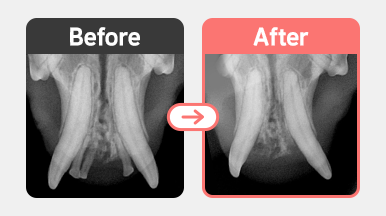

구강검진 결과, 앞니 부위에 PD3 이상 치주염이 확인되었고, 치아 주위 조직 파괴 및 치은 퇴축이 동반되어 있었습니다.

PD3 이상은 치아 보존이 어려워질 수 있는 단계로, 호흡마취 하에 발치를 진행하였으며 수술 후 빠르게 회복되었습니다.

3살 코숏 고양이 구강검진 – 앞니 부위에 PD3 이상 치주염 소견 확인

치주염 진행으로 인한 치은 퇴축 및 치아 조직 파괴 확인